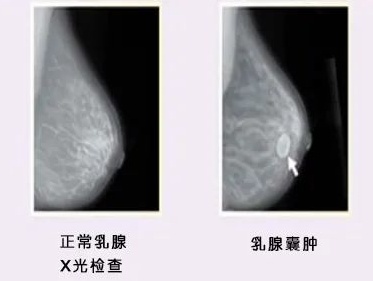

乳腺囊肿

如果肿块为圆形或椭圆形小肿块

摸起来质地类似于新鲜葡萄

那可能是